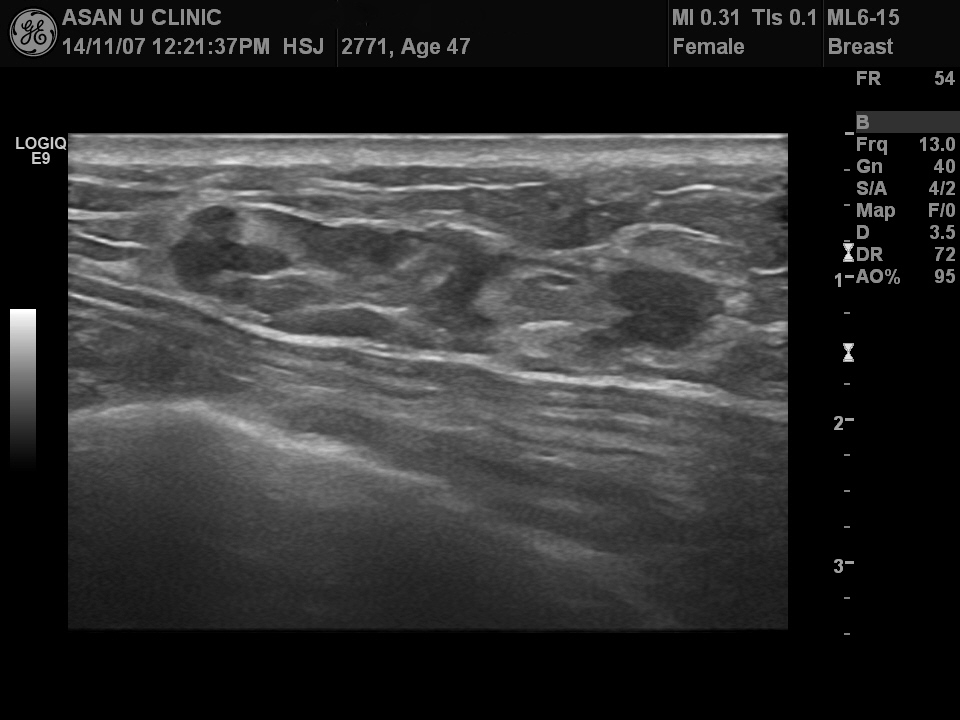

좌측 유방 상외측에 갑자기 만져지는 혹이 있어 내원한 47세 여성입니다.

본원유방초음파상 만져지는 5cm이상의 혹 외에도

상내측에 그림과 같은

1cm 전후의 결절들이 더 있었고

각각의 조직검사를 실시하였으며

안타깝게도 모두 침윤성 유관암으로 진단되셨습니다.